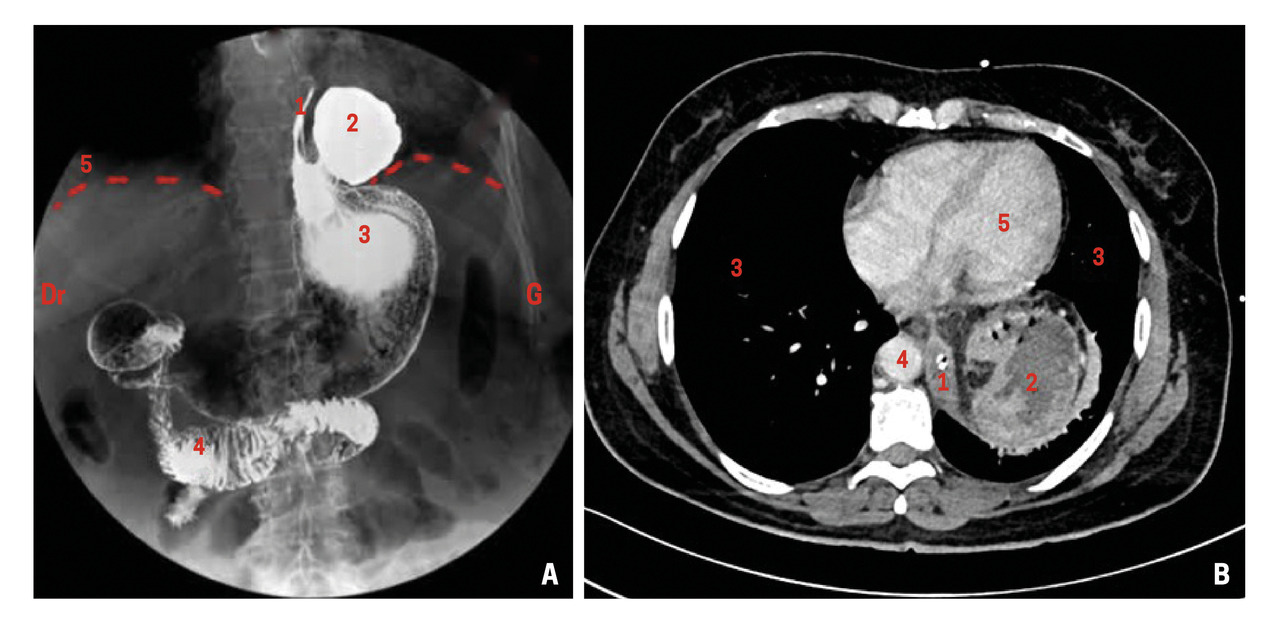

Les examens complémentaires réalisés en cas de suspicion de hernie hiatale associent une gastroscopie, permettant d’exclure des lésions œsophagiennes ou gastriques intraluminales, et un bilan d’imagerie morphologique comprenant un transit œso-gastro-duodénal (fig. 2A) ou un scanner thoraco-abdominal (fig. 2B).7